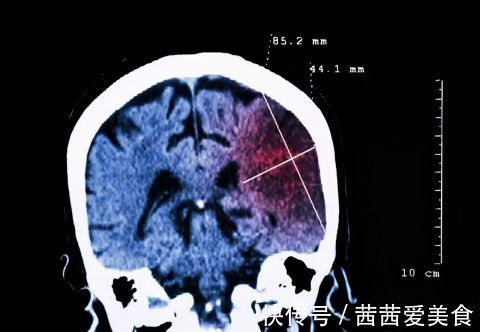

高血压病友:您是否知道,一天中哪个时刻最危险?最容易因高血压出现危急心血管病变?答案是:清晨。清晨,人体血压有自然升高的趋势。即便您一天中,其他时间的血压都正常,依然有较大风险出现心肌梗死、脑卒中等危急事件。

对于高血压患者而言,即便平时血压控制良好,但这10-20%的增幅,依然会再次将您置于险境之中!判断标准:若在家测量的清晨血压≥135/85mmHg,即为清晨高血压。清晨血压超标:值得每位高血压患者警惕的信号!在我国,约60%高血压患者的清晨血压都超标。这会对心脏、大脑、肾脏和血管等带来严重损害。总的来看,清晨高血压:是心血管事件高发的首要危险因素。约有40%心肌梗死和29%心脏性猝死发生在清晨时段;是脑卒中最强的独立危险因素,该时段脑卒中的发生率是其他时段的3~4倍;会诱发无症状的动脉硬化症、颈动脉内膜增厚斑块。数据显示清晨高血压患者颈动脉粥样硬化的相对风险增加5倍;会加重慢性肾脏病患者肾功能损伤。如何降低清晨高血压?以下5种措施,每多做一个,血压降一分(1)调整用药,确保清晨血药浓度达标很多人会选择晨起后吃降压药。但在没起之前,体内的降压药浓度经过24小时的消耗,已降至最低,无法遏制清晨血压升高的趋势。建议你做好这2个小措施:选用24小时的长效降压药,确保清晨时血液中的有效药物浓度达标。可根据清晨和夜间血压情况,在医师的指导下,将服药时间改在下午4-6点。确保在早晨醒来时,体内的有效药物浓度能控制住清晨高血压。